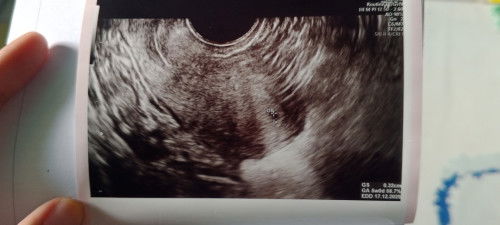

USG BELUM KELIATAN KANTONG

Usia kandungan 4minggu, di USG belum keliatan kantongnya. Disuruh balik usg 2minggu lagi. Normal kan ya?

aku baru USG mam..usia 4w5d pakai abdomen atau perut emang belum kelihatan kantong nya. trus aku minta usg transvaginal saja dan baru terlihat kantongnya masih samar dan sangat kecil